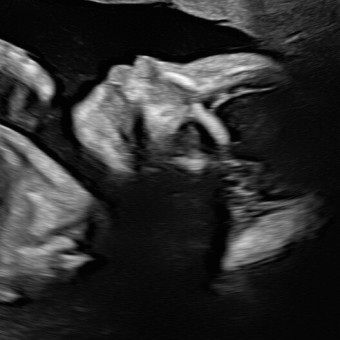

✨🩵✨ lil’ man ✨🩵✨

Michaela Engel & Phil Patterson

July 14, 2025